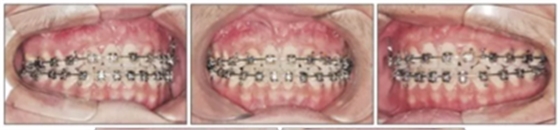

第三階段(圖7,表2)

19歲2月時行固定矯治排齊下頜牙列建立穩(wěn)定的咬合及正常的覆合覆蓋,持續(xù)1年10月。摘除后(21歲)上下頜用固定保持器,上頜牙弓用Hawley保持器。